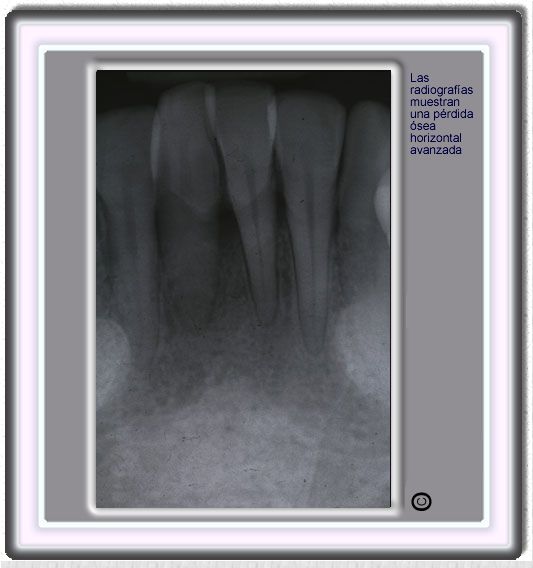

image 307